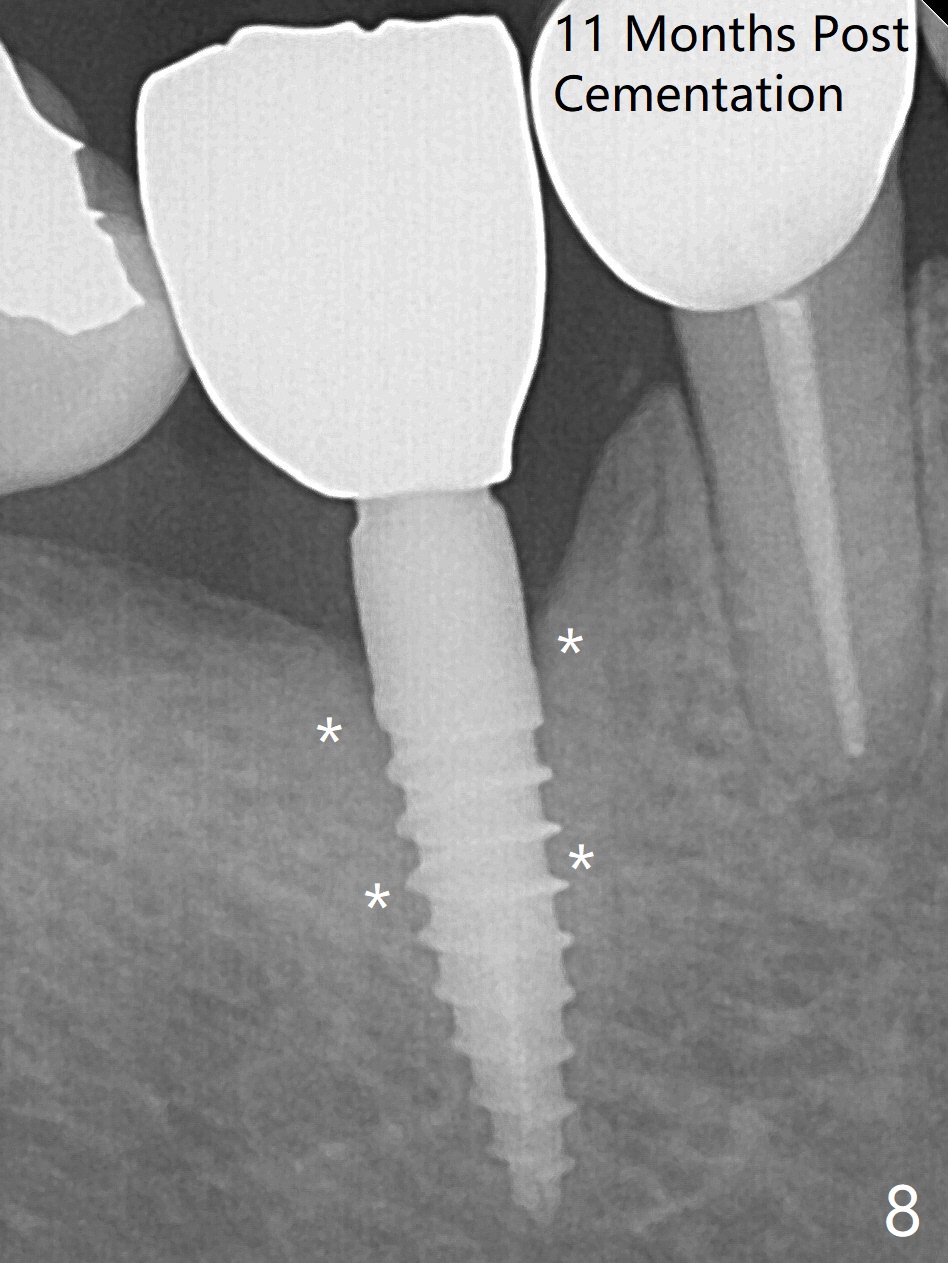

Incision reveals a narrow ridge and a narrow mesiodistal space at #30 (Fig.1). It seems that a 1-piece implant is indicated. Due to limited mouth opening, a 1.2 mm drill is unstable in place after use for 10 mm; instead a 1.5 mm drill is able to be inserted for 8 mm (Fig.2). A 3x10(2) mm 1-piece dummy implant is placed with 40 Ncm at an apparently acceptable level (Fig.3 >). Clinically a few threads are exposed buccally. When a definitive implant with the same dimension is inserted with 45 Ncm, it looks seated too deep (Fig.4,5). The latter is noted after suturing. The implant is backed up for a few turns so that the length of the abutment appears a little more reasonable. Introspectively, a 4 mm cuff should have been used after ridge reduction. Although there is no bone loss 4 months postop (Fig.6), the abutment margin (Fig.7 arrow) is subgingival (red dashed line: gingival margin). Diode laser is used for gingivectomy prior to impression. The bone density around the implant increases 11 months post cementation (Fig.8 *), probably related to recurrent #18 infection. The patient uses floss after meal.